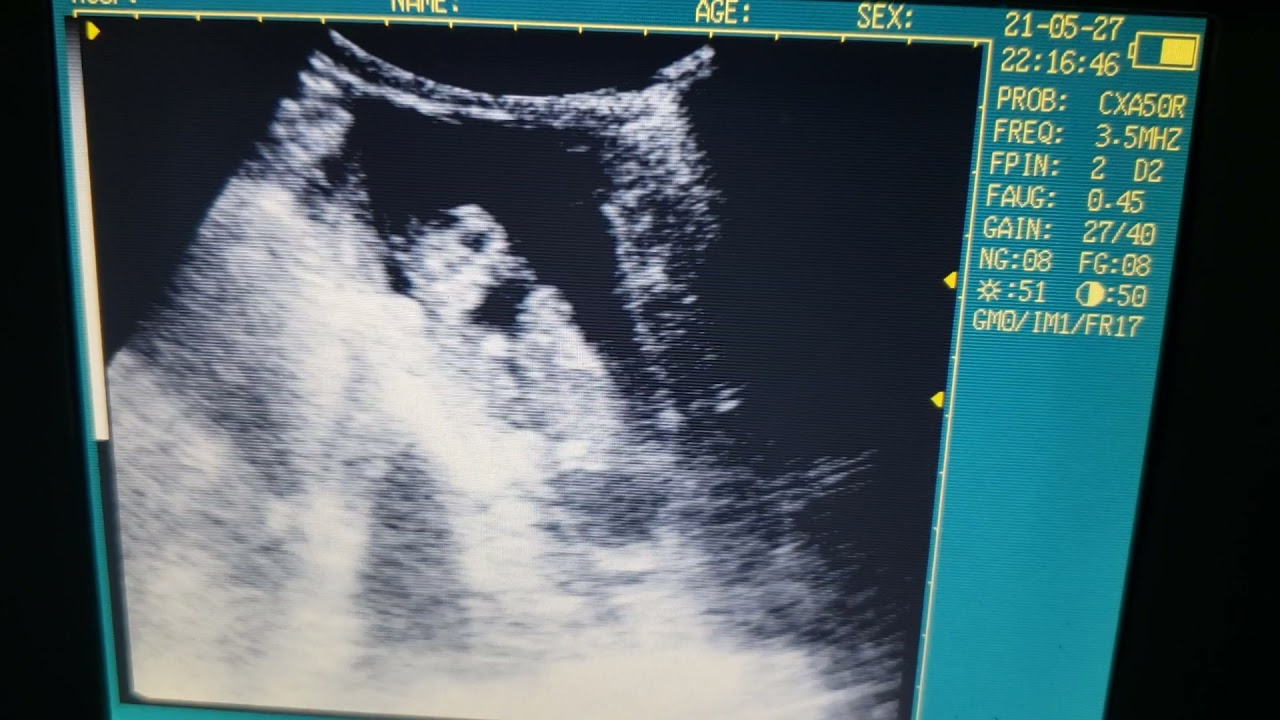

Scan on 7 week dachshund Animal Ultrasound Association

Dachshund Ultrasound The pups continue to grow during this stage. During week 4, visit the vet once more to confirm the pregnancy through ultrasound examination. Your vet can perform an ultrasound to confirm the pregnancy and check the health of the embryos. The vet should be able to determine the number of puppies your dachshund will have, as well as any potential abnormalities. You might notice that your dog’s nipples are slightly enlarged. The best way to determine if your dachshund is pregnant is with a blood test performed at the veterinarian. They are visible on an ultrasound, particularly their little spines. Ultrasound of a dachshund at approximately 33 days gestation. Take your dachshund to the vet for a blood test or ultrasound if you suspect she is pregnant. At this stage, the fetuses are about the size of a. The spine and the eyes start to develop, and their faces begin to shape up. The pups continue to grow during this stage. Around two to three weeks after.

From www.animalultrasoundassociation.org

Scan on 7 week dachshund Animal Ultrasound Association Dachshund Ultrasound Ultrasound of a dachshund at approximately 33 days gestation. They are visible on an ultrasound, particularly their little spines. The vet should be able to determine the number of puppies your dachshund will have, as well as any potential abnormalities. The pups continue to grow during this stage. Your vet can perform an ultrasound to confirm the pregnancy and check. Dachshund Ultrasound.